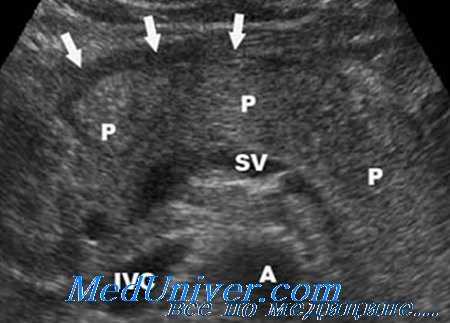

Обязательное условие выполнения пункционных процедур под контролем ультразвука — четкая визуализация жидкостного очага с оценкой его топографии.

Но тонкоигольные пункции (одно- или многократные) эффективны лишь при очагах не более 50 мл. Это оправдано, когда по ходу предполагаемого движения иглы располагается двенадцатиперстная кишка.

Дренирование обеспечивает пролонгированный санационный эффект.

Контроль эффективности пункционного вмешательства осуществляется при помощи динамических ультразвуковых исследований и фистулографий.

Обязательно проводится микробиологическое исследование отделяемого для определения чувствительности флоры к антибактериальным препаратам. При осумкованных жидкостных образованиях может быть установлено несколько дренажей для активного промывания очага. Для создания более адекватного оттока гноя возможно проведение бужирования дренажного канала с установлением трубок большего диаметра.